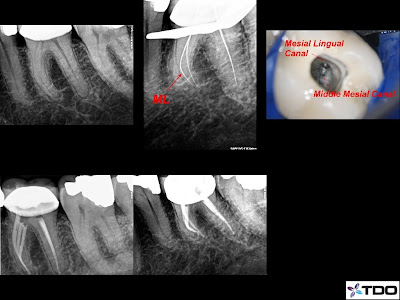

This patient presented with severe pain.

Root canal retreatment was initiated on tooth number 30. Her symptoms disappeared after the first visit, after locating and instrumenting the missed DL canal. There was also a Middle Mesial canal.

Interestingly, the final radiograph doesn't look that different.